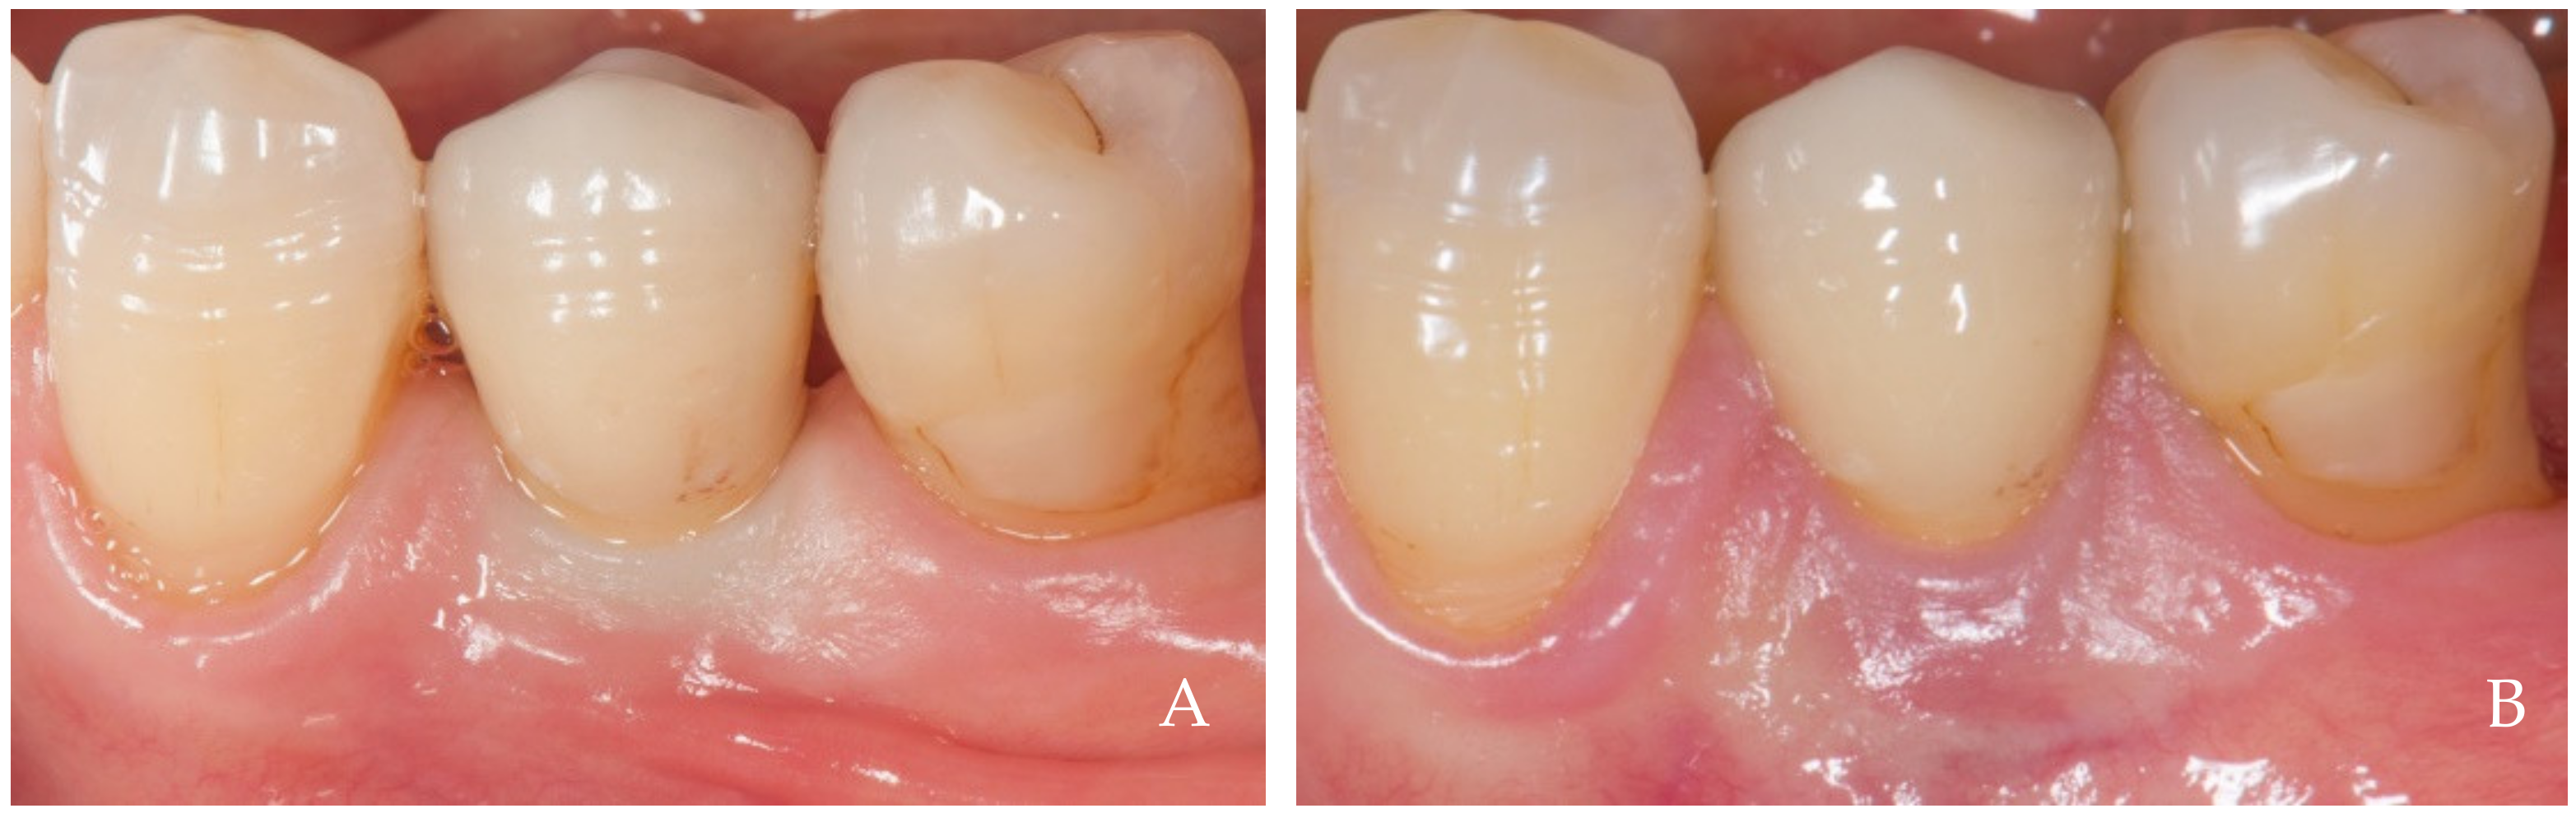

2. Clinical Examples of Oral Soft Tissue Growth